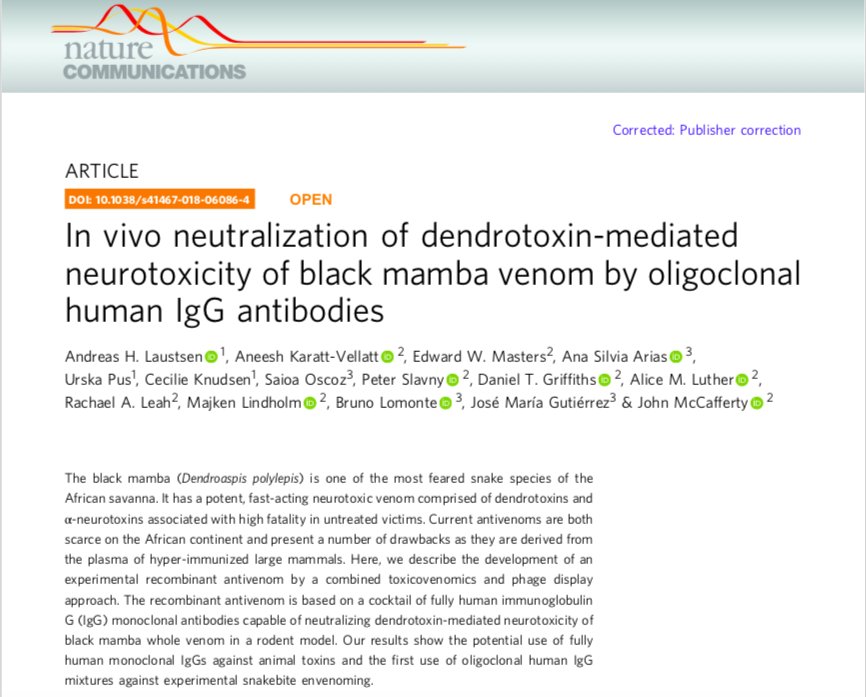

Humbled to see that some opine that our work on

#antivenom based on human oligoclonal antibodies targeting#blackmamba#toxins is among the top 10 biopharma breakthroughs of 2018: https://www.technologynetworks.com/drug-discovery/lists/top-10-biopharma-news-stories-of-2018-313185 …@A_KarattVellatt@NatureComms@UniversidadCR@DTUtweet@DTUbioengineerpic.twitter.com/V9zinn9348 ಧನ್ಯವಾದಗಳು. Twitter ಇದನ್ನು ನಿಮ್ಮ ಕಾಲರೇಖೆಯನ್ನು ಉತ್ತಮಗೊಳಿಸಲು ಬಳಸುತ್ತದೆ. ರದ್ದುಗೊಳಿಸುರದ್ದುಗೊಳಿಸು

NatureCommunications ಅವರು ಮರುಟ್ವೀಟಿಸಿದ್ದಾರೆ

@AndreasLaustsen et al's breakthrough in snake envenoming published earlier this year in@NatureComms is on Technology Networks' "Top 10 Biopharma News Stories of 2018": https://www.technologynetworks.com/drug-discovery/lists/top-10-biopharma-news-stories-of-2018-313185 …@Tech_Networks@DTUtweet@WHO#researchhighlightಧನ್ಯವಾದಗಳು. Twitter ಇದನ್ನು ನಿಮ್ಮ ಕಾಲರೇಖೆಯನ್ನು ಉತ್ತಮಗೊಳಿಸಲು ಬಳಸುತ್ತದೆ. ರದ್ದುಗೊಳಿಸುರದ್ದುಗೊಳಿಸು -